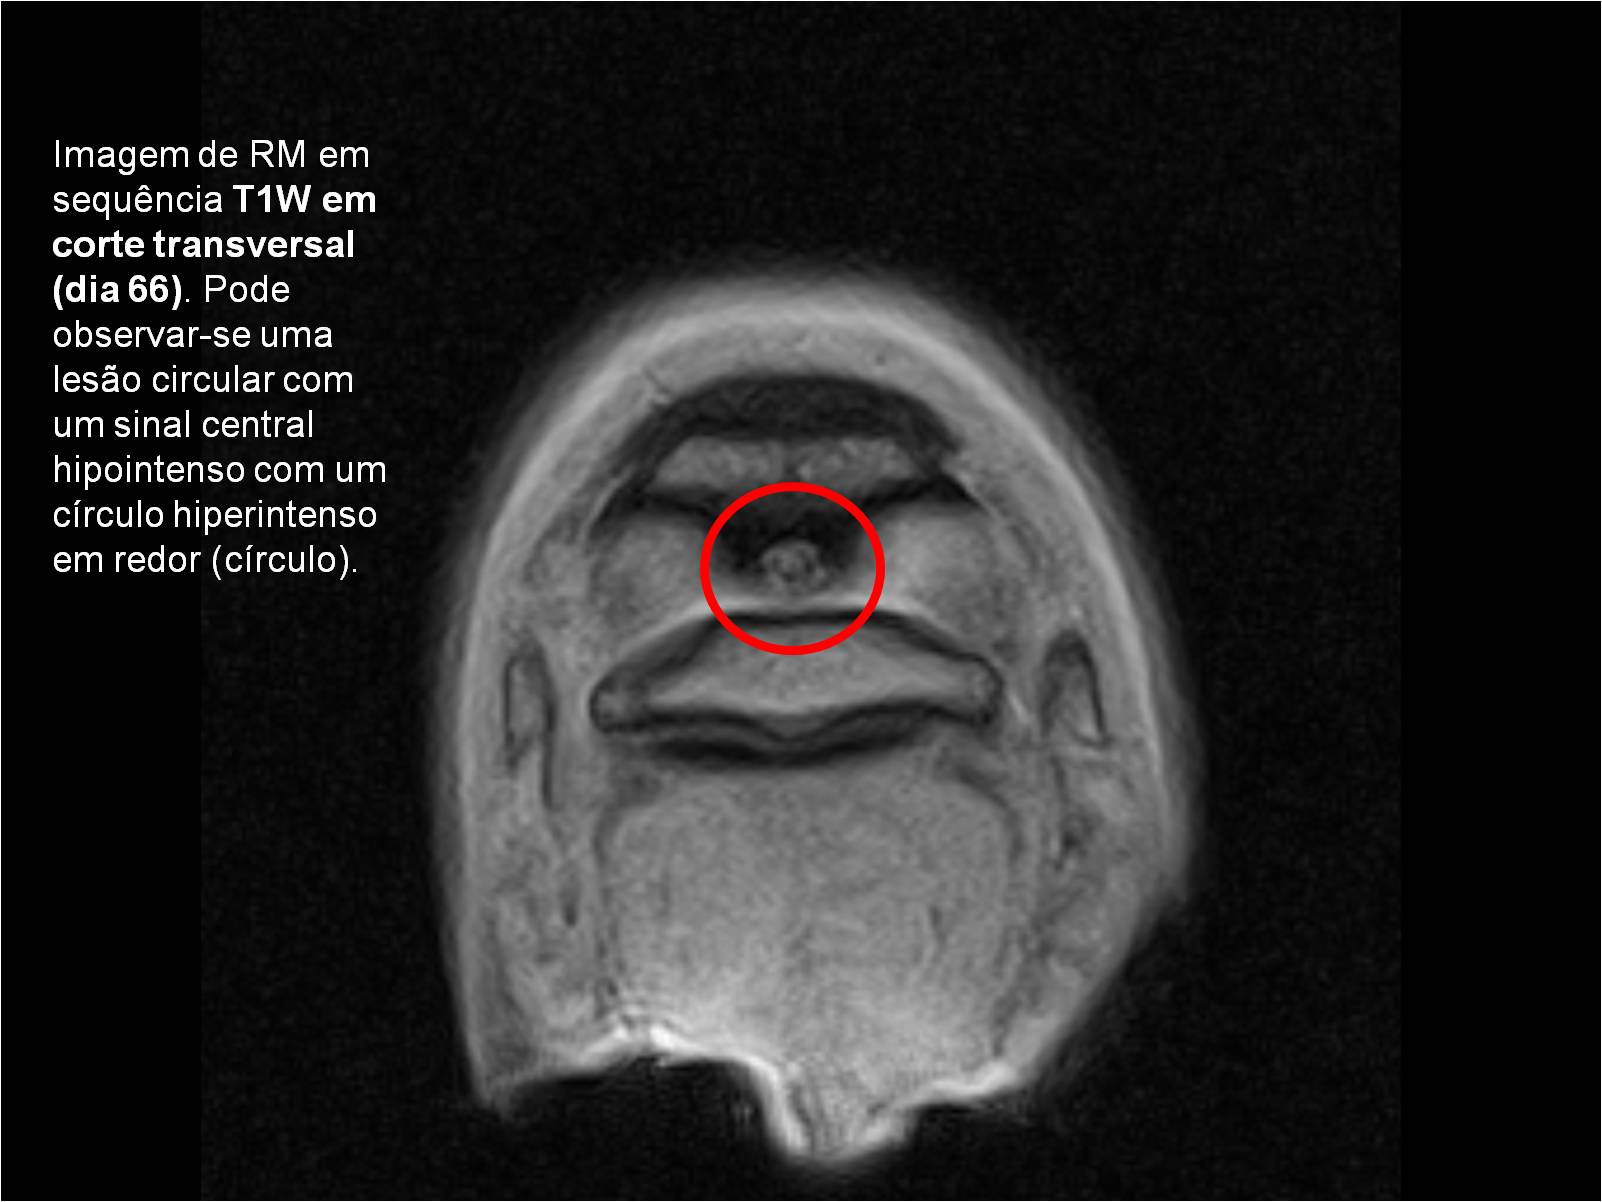

Publisher: Universidade de Évora

Abstract: O relatório de estágio encontra-se estruturado em três partes distintas. A primeira parte faz a caracterização das infraestruturas e funcionamento do Hospital Veterinário de Equinos de Lüsche, Oldenburg, Alemanha, assim como a análise casuística dos casos clínicos acompanhados durante os 6 meses de estágio. A segunda parte consiste de uma revisão bibliográfica sobre quistos do osso subcondral em equinos. Por fim, a terceira parte consta da apresentação e discussão de um caso clínico, nomeadamente o diagnóstico e acompanhamento imagiológico, por ressonância magnética, de um quisto subcondral na terceira falange num cavalo adulto; ### Abstract Equine Practice- Subcondral bone cyst of the third phalanx This internship report is divided in three parts. The first part characterizes the infrastructure and function of the Equine Hospital Lüsche, Oldenburg, Germany, as well as the casuistic of the clinical cases accompanied during the 6 month internship. The second part consists in a bibliographic review of cystic lesions of the subchondral bone in equines. The third part consists in a case report, the diagnostic and imagiological accompaniment, by use of magnetic resonance imaging, of a subchondral bone cyst in the distal phalanx of an adult equine.